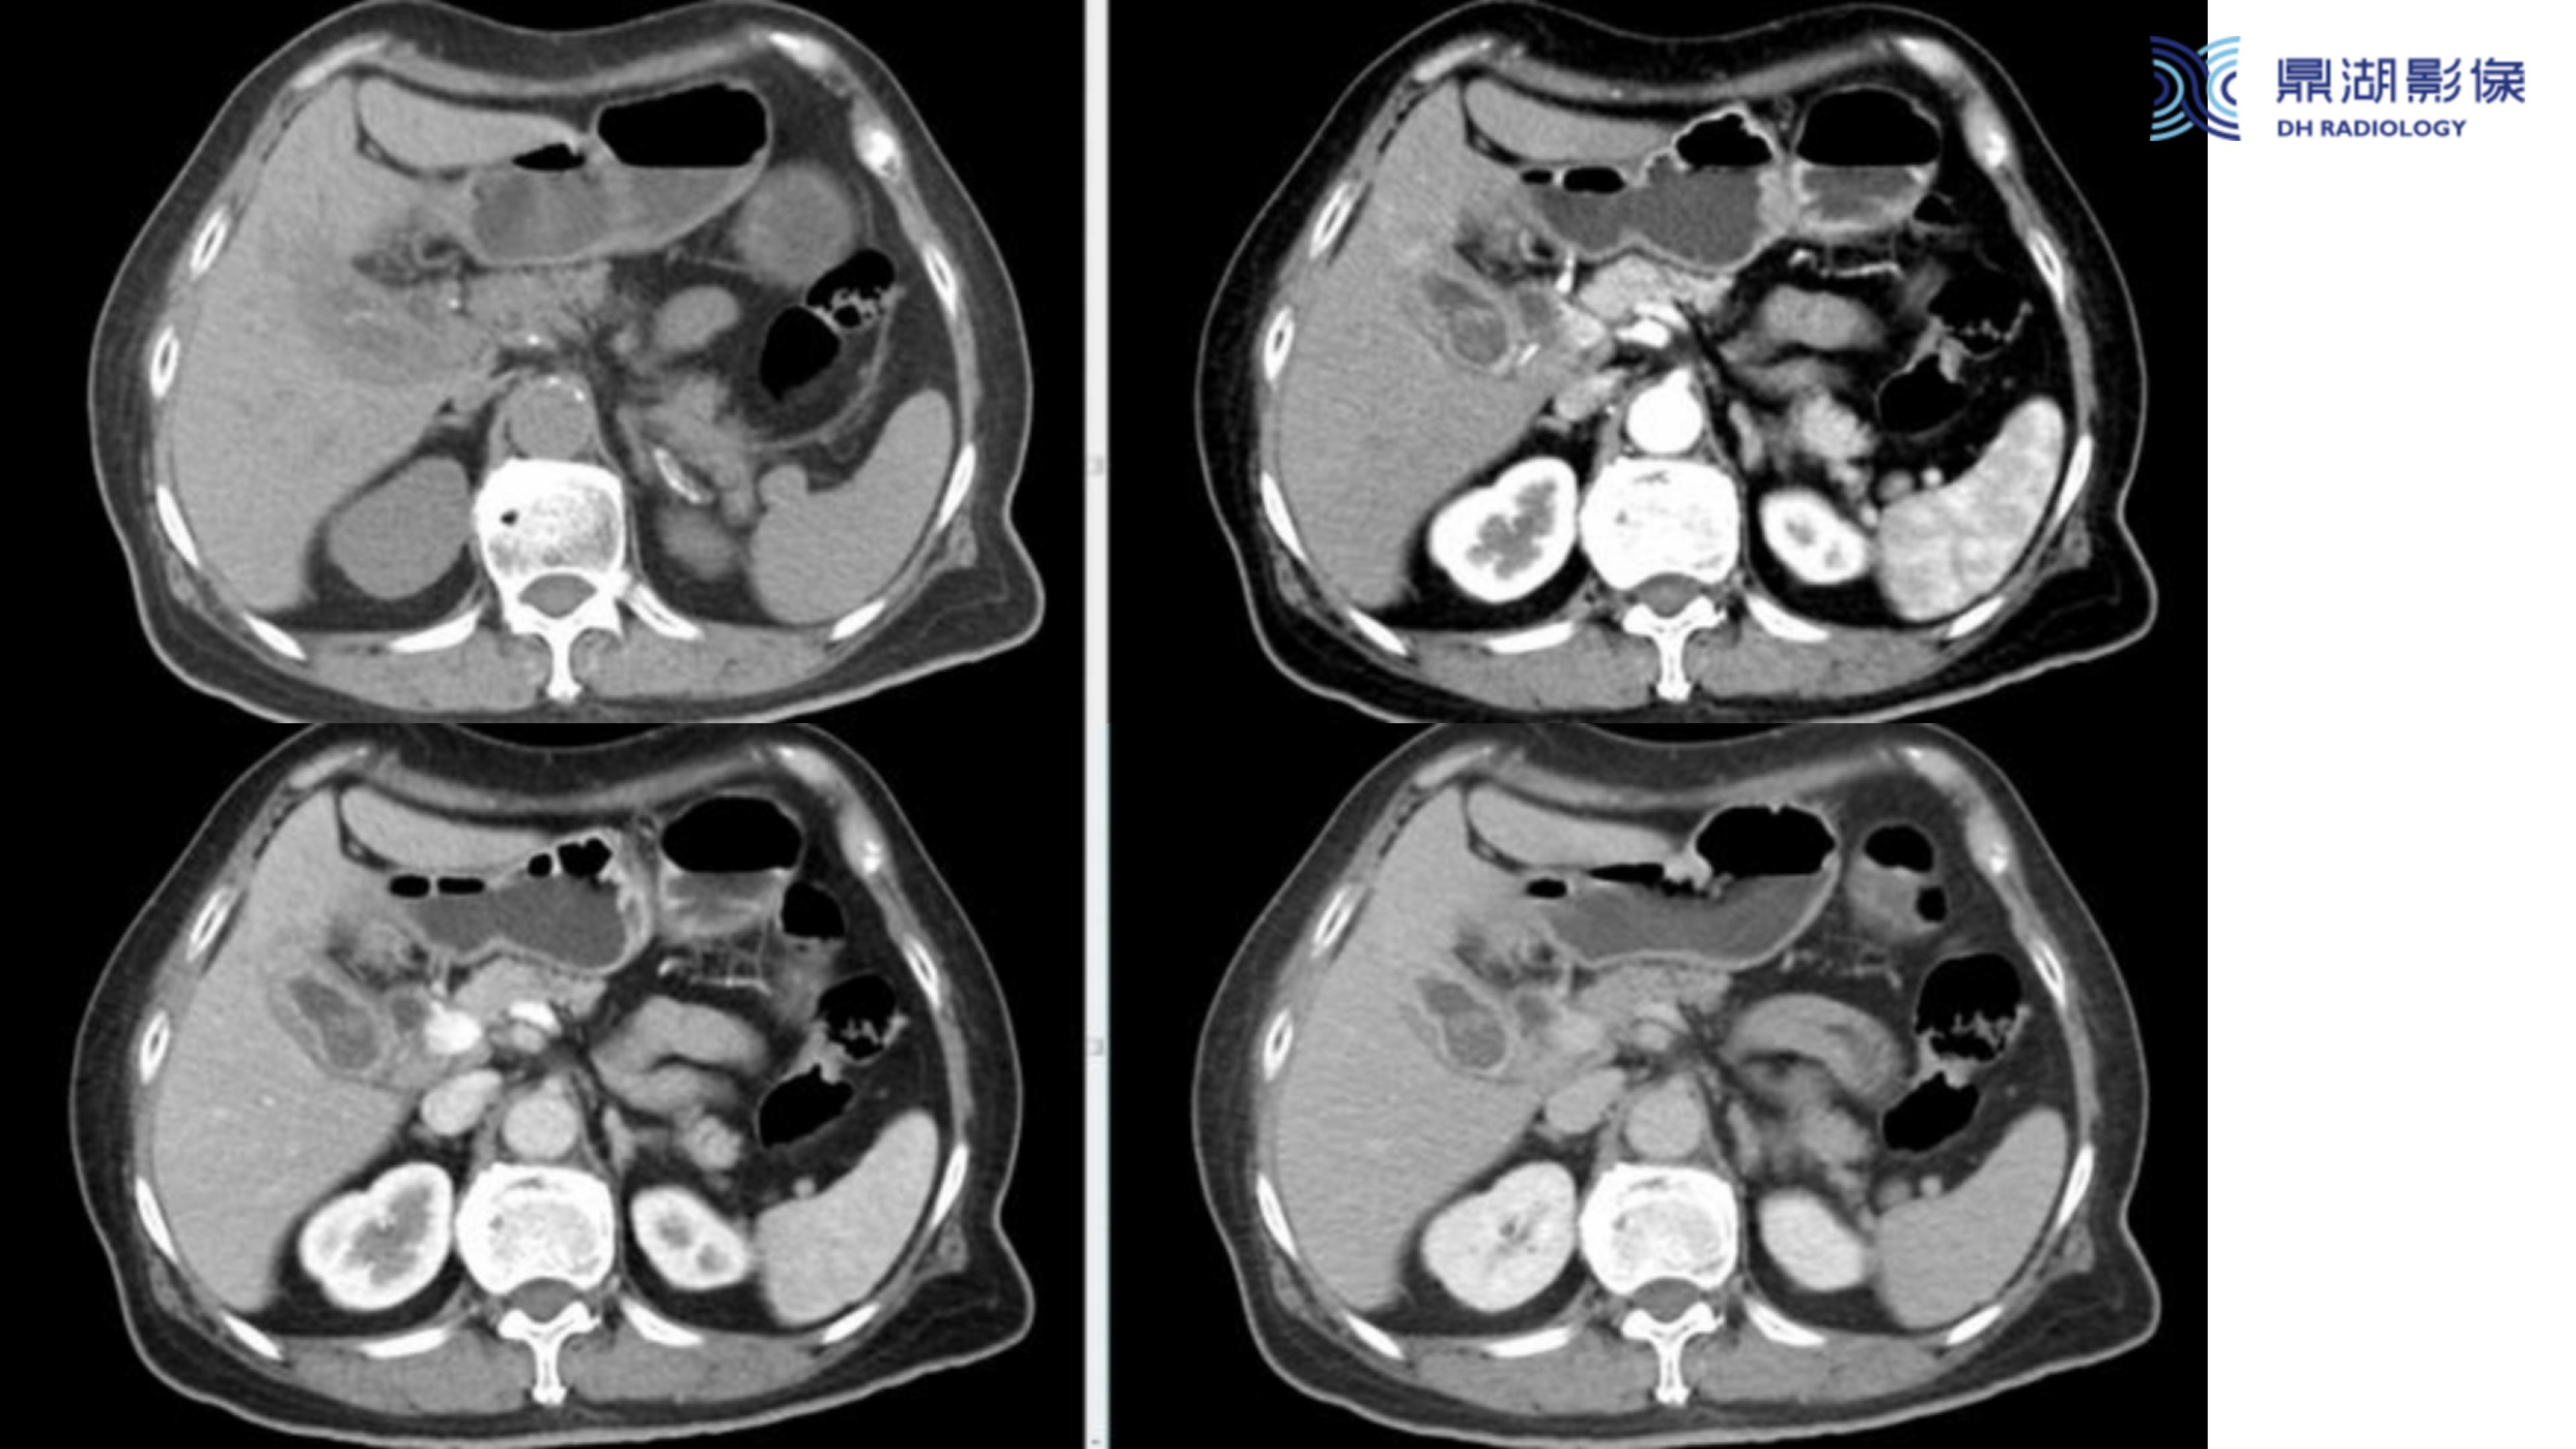

胆囊癌-鼎湖社群读片病例